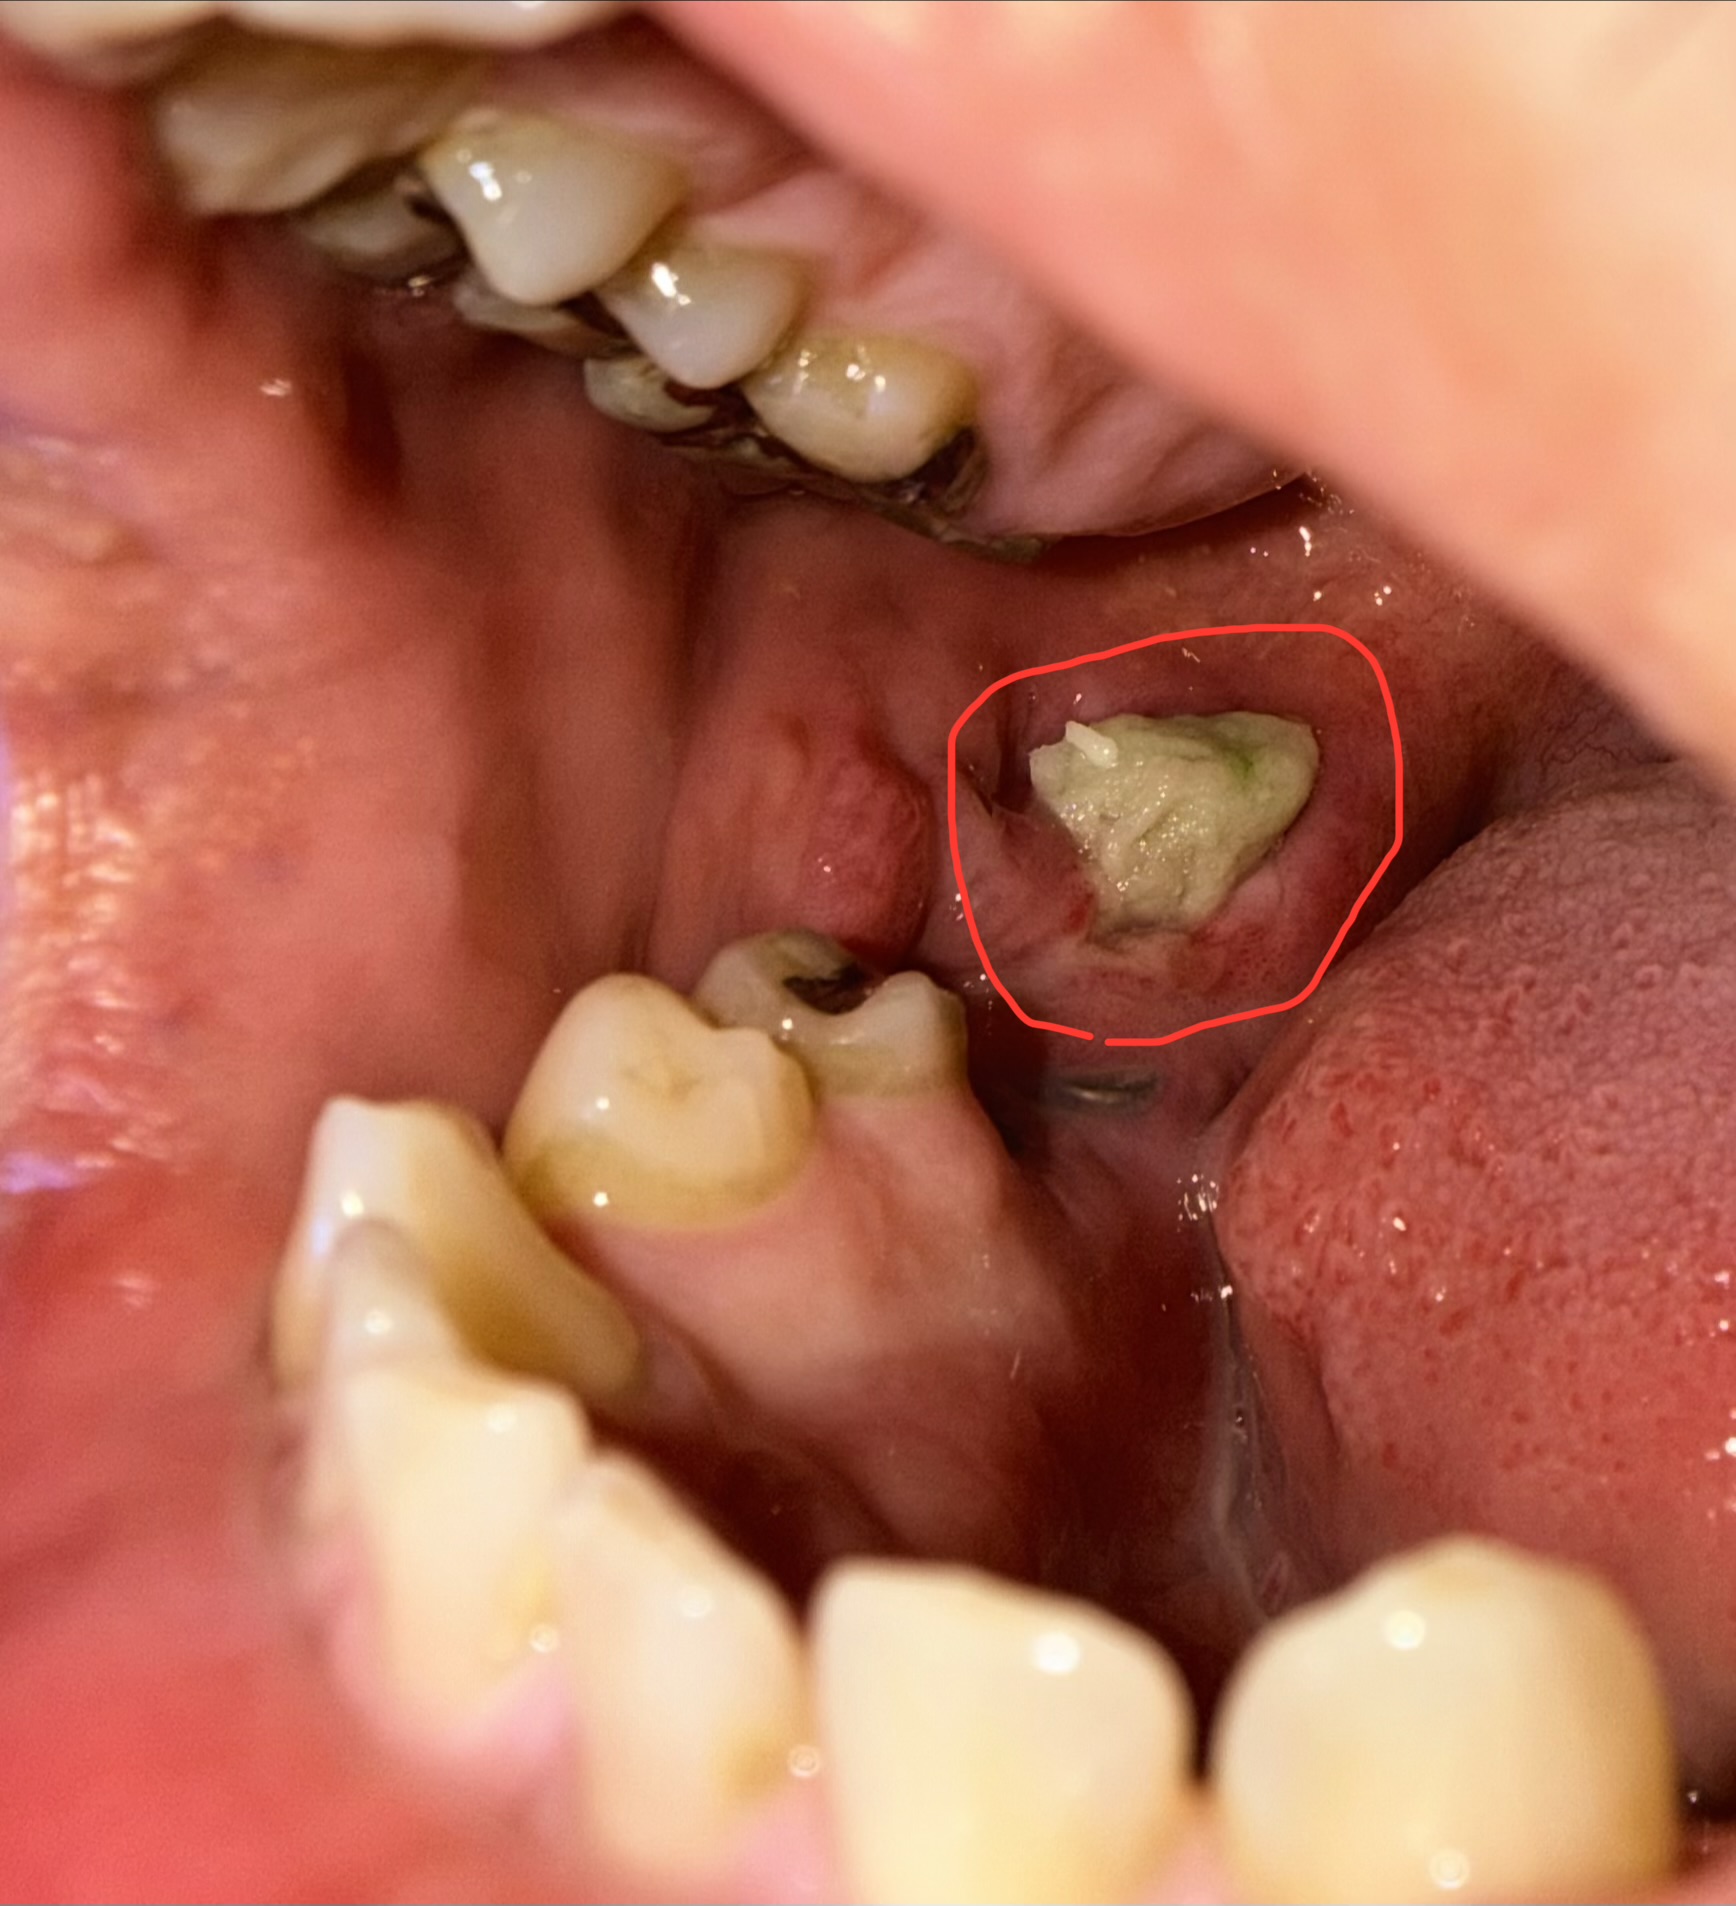

抜歯後の部分に白いかたまりがあります。放置していても問題ないですか?